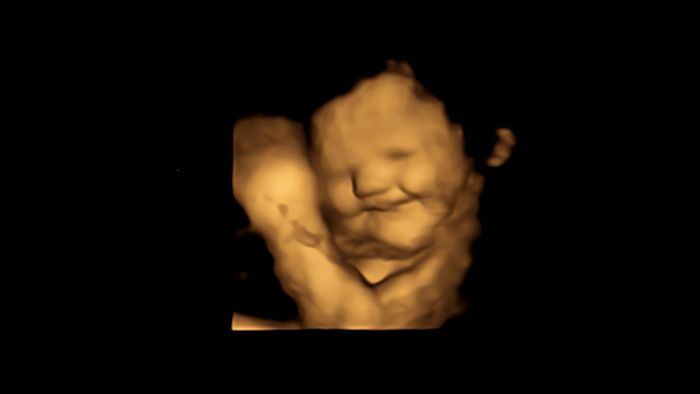

图像:笑脸反应扫描图像

接触胡萝卜的胎儿表现出更多的“笑脸”反应,而接触羽衣甘蓝的胎儿则表现出更多的“哭脸”反应。

两种味道的胎儿的面部反应,与没有接触任何一种味道的对照组胎儿的面部反应相比,表明接触少量胡萝卜或羽衣甘蓝味道就足以刺激反应。